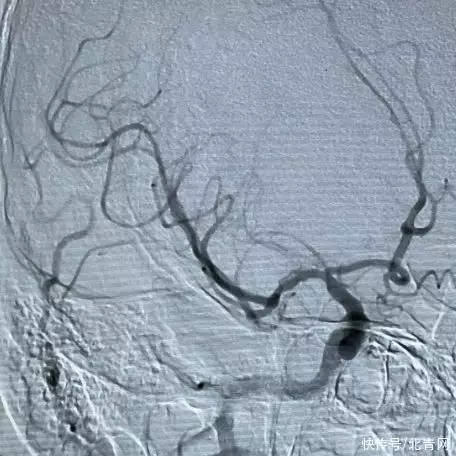

与死亡擦肩而过住院10天后康复根据阿杰的病情,医生马上给阿杰实施静脉溶栓和急诊介入取栓手术治疗,最终顺利取出了堵塞脑血管的血栓,开通了闭塞血管。

左图:开通后的血管入院2小时后,阿杰就恢复了“自由身”,左半边身子可以重新活动了10天后顺利康复出院,并且完全可以活动自如了““医生当时说坏一点的后果就是偏瘫、甚至死亡现在这个结果真的是万幸”虽然结果顺利,但回忆起被确诊中风后的那几个小时,阿杰还是心有余悸。